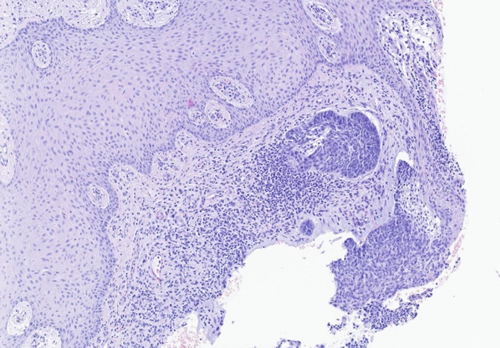

El resultado de anatomía patológica confirmó la sospecha de malignidad en el material remitido, informando de lesión compatible con carcinoma basocelular de patrón nodular (Figura 4), por lo que se deriva a servicio de dermatología para su evaluación completa y tratamiento quirúrgico con valoración de posterior tratamiento coadyuvante, si procede.

Figura 4. Imagen anatomopatológica de la lesión tumoral.